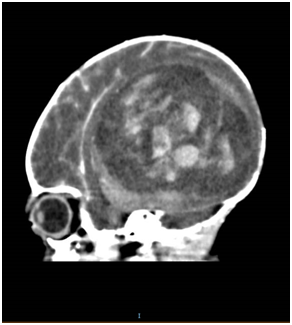

Ultrasound of the brain on day 1 of life showed a right parieto-occipital hypoechoic mass of 4.8 cm with 2.1 cm hyperechoic density (Figure 2). Magnetic Resonance Imaging (MRI) of the brain showed a large haemorrhagic right temporo-occipital mass measuring 5.6 cm, with early hydrocephalus, suspicious of a supratentorial primitive neuroectodermal tumour (PNET) (Figure 3).

Figure 2 Ultrasound brain done on day 1 of life showed a right parieto-occipital hypoechoic mass 4.8 x 4.0 cm, with 2.1 x 1.2 cm hyperechoic density compressing right ventricle with midline shift to left and abnormal grey-white matter differentiation.